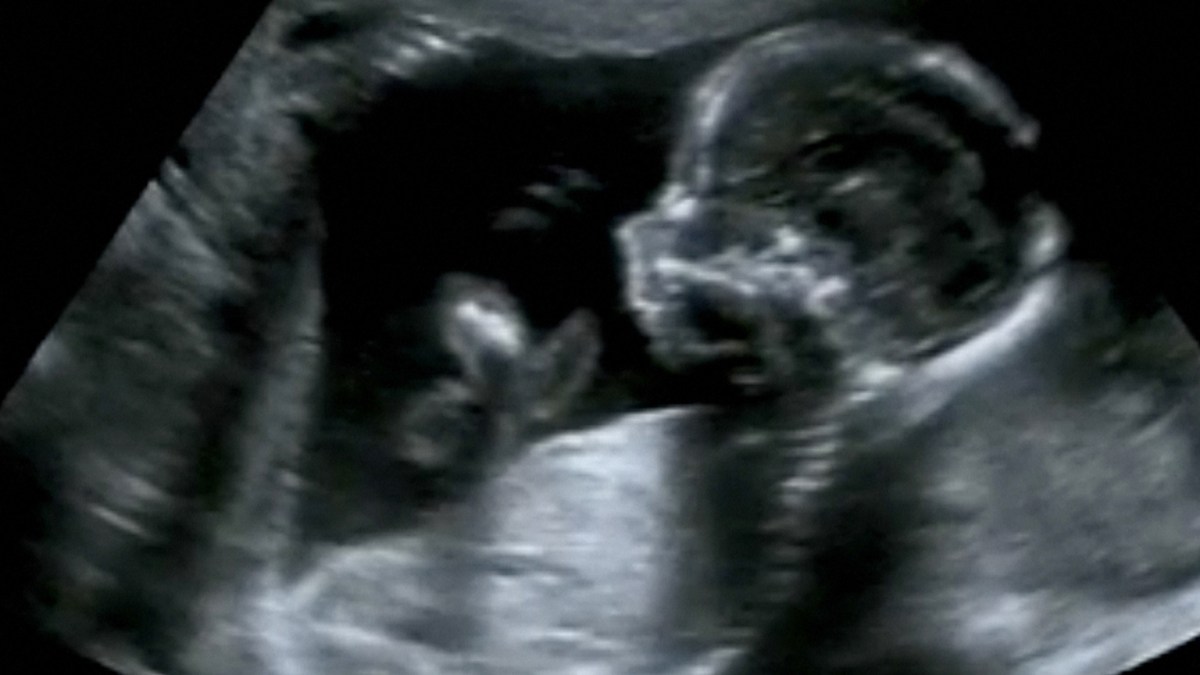

In the U.S., anencephaly is now regularly screened for in a first trimester ultrasound. If the condition is spotted, expecting parents are apprised of the devastating prognosis and their options: either terminate the pregnancy or carry it to term. In two recent studies, researchers specializing in midwifery and obstetrics nursing urged medical providers not to force parents into a hasty decision to terminate the pregnancy. Simply give parents the blunt, painful facts as gently and compassionately as possible and allow them time to make an informed decision once the initial shock has subsided, they recommend.